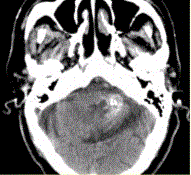

问题 男性,80岁,左耳听力下降伴头晕半年。头CT显示如下图。 需与海绵状血管瘤鉴别的病变包括

选项 A.弥漫性轴索损伤 B.高血压性微出血 C.血管淀粉样变 D.毛细血管扩张症 E.AVM F.成胶质细胞瘤伴出血 G.钙化性肿瘤,如少枝胶质细胞瘤

答案 ABCDEFG